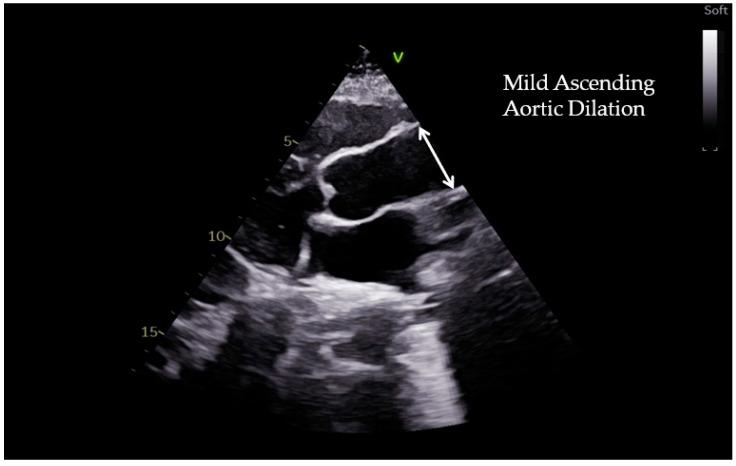

胸主动脉扩张是一种渐进性疾病,由衰老和许多病理状况(如结缔组织病、炎症性疾病、剪切应力紊乱、严重瓣膜性心脏病)引起,这些病理状况会导致弹性特性发生退行性变化,进而导致主动脉壁弹性和顺应性丧失。在运动员中也可能观察到轻度主动脉根部扩大,这被认为是对常规运动训练的正常适应。另一方面,对于具有特定遗传背景的个体,如携带与马凡综合征或其他遗传性主动脉疾病相关基因变异的个体,高强度体育活动可能会导致主动脉过度扩大并引发急性主动脉夹层。评估主动脉瓣和主动脉根部直径,以及检测遗传性主动脉疾病的致病突变后,应针对运动资格做出个性化决策。此外,遗传性主动脉疾病患者运动相关的主动脉并发症风险特征尚不明确,而且往往难以对每位运动员进行分层。本综述旨在描述规律体育活动与主动脉扩张之间的关系,重点关注二叶式主动脉瓣和遗传性主动脉疾病患者,并讨论其对主动脉疾病进展和运动参与的影响。